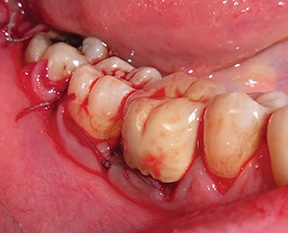

The flap was then closed with a combination of horizontal mattress and interrupted 4-0 polyester sutures (Fig. 20).

After a four-month healing period, a full-thickness flap was raised to evaluate the outcome (Fig. 21).

Fig. 20: Recipient site closed with double-layer sutures

Block by Block

Fig. 21: Full-thickness flap raised at surgical re-entry